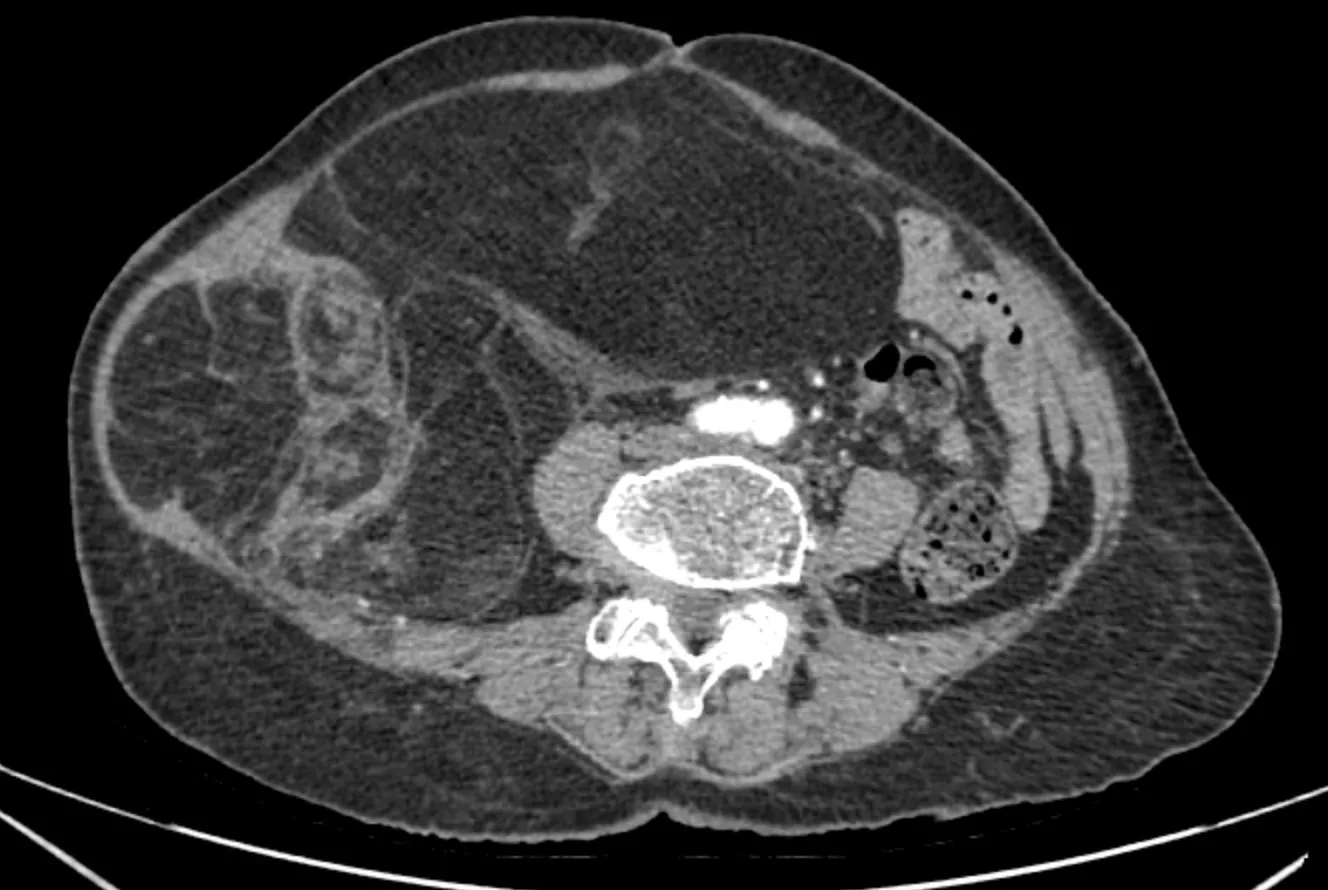

Kết quả chẩn đoán hình ảnh (CT ổ bụng có thuốc cản quang) cho thấy, khối choán chỗ sau phúc mạc, kích thước 28 × 15cm, cấu trúc hỗn hợp tổ chức mỡ – đặc, đè đẩy tạng trong ổ bụng nhưng không có dấu hiệu xâm lấn các tạng lân cận. Kết hợp lâm sàng và hình ảnh học, bệnh nhân được chẩn đoán sarcoma mỡ sau phúc mạc.

Phim chụp CT ổ bụng của bệnh nhân N.T.T.